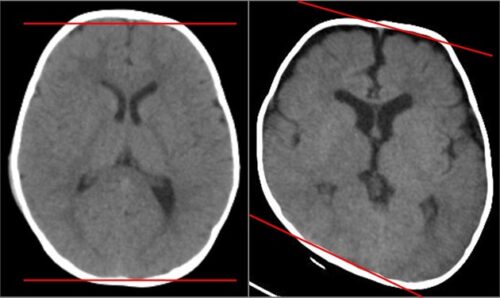

يُعد تشوه الجمجمة الوضعي أو ما يُعرف بتسطح الرأس عند الرضع (Plagiocephaly) من الحالات الشائعة في السنوات الأخيرة، خاصة بعد توصية الأطباء بوضعية النوم على الظهر للوقاية من متلازمة موت الرضع المفاجئ. ورغم أن هذه الوضعية تحمي الطفل من مخاطر خطيرة، إلا أنها قد تؤدي إلى ضغط مستمر على جزء محدد من الجمجمة، مما يسبب تغيرًا في شكل الرأس.

مدى دقة تصنيف أرجنتا (Argenta Classification): وهو نظام طبي يُستخدم لتحديد درجة تشوه الجمجمة عند الرضع.

شملت الدراسة الأطفال الذين يعانون من تسطح الرأس من الدرجة الثانية حتى الخامسة حسب تصنيف أرجنتا.

كلما ارتفعت درجة التشوه (النوع الثالث، الرابع، الخامس) احتاج الطفل فترة أطول للتحسن مقارنة بالحالات الخفيفة (الدرجة الثانية).

العمر لم يكن عائقًا! حتى الأطفال الذين بدأوا العلاج بعد عمر 12 شهرًا أظهروا نتائج مشابهة جدًا للأطفال الذين بدأوا العلاج في عمر 3 أشهر أو أقل.

نسبة النجاح في الوصول إلى شكل رأس طبيعي (النوع الأول) بلغت 81.6%، وهي نسبة ممتازة تؤكد فعالية العلاج بالخوذة.

العلاج بالخوذة يُعتبر فعالًا وآمنًا للأطفال من عمر 0 إلى 14 شهرًا. وقد أثبتت الدراسات أن تصنيف أرجنتا أداة دقيقة لتحديد شدة الحالة وتوقع مدة العلاج. والأهم أن النتائج الممتازة تتحقق بالالتزام بالخوذة ومتابعة الطبيب.